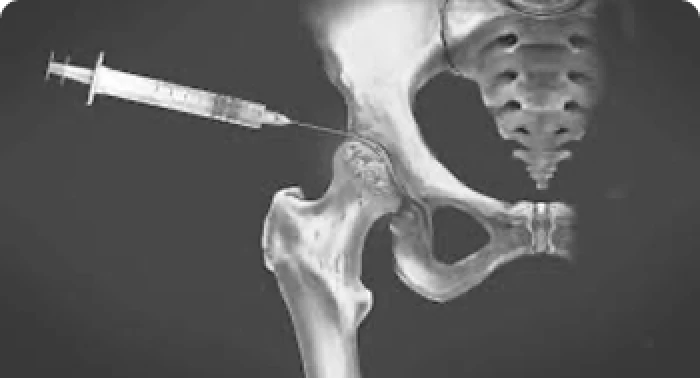

Tratamento Conservador em Medicina Regenerativa

Nem todo problema no quadril precisa de cirurgia. Infiltrações, fisioterapia direcionada e medicamentos podem resolver muitos casos.